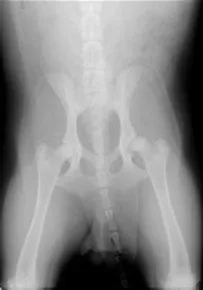

Radiology is a frequently used diagnostic tool which provides our veterinarians with a view of the internal body systems and the skeletal system. Radiographs can usually be processed while you wait.